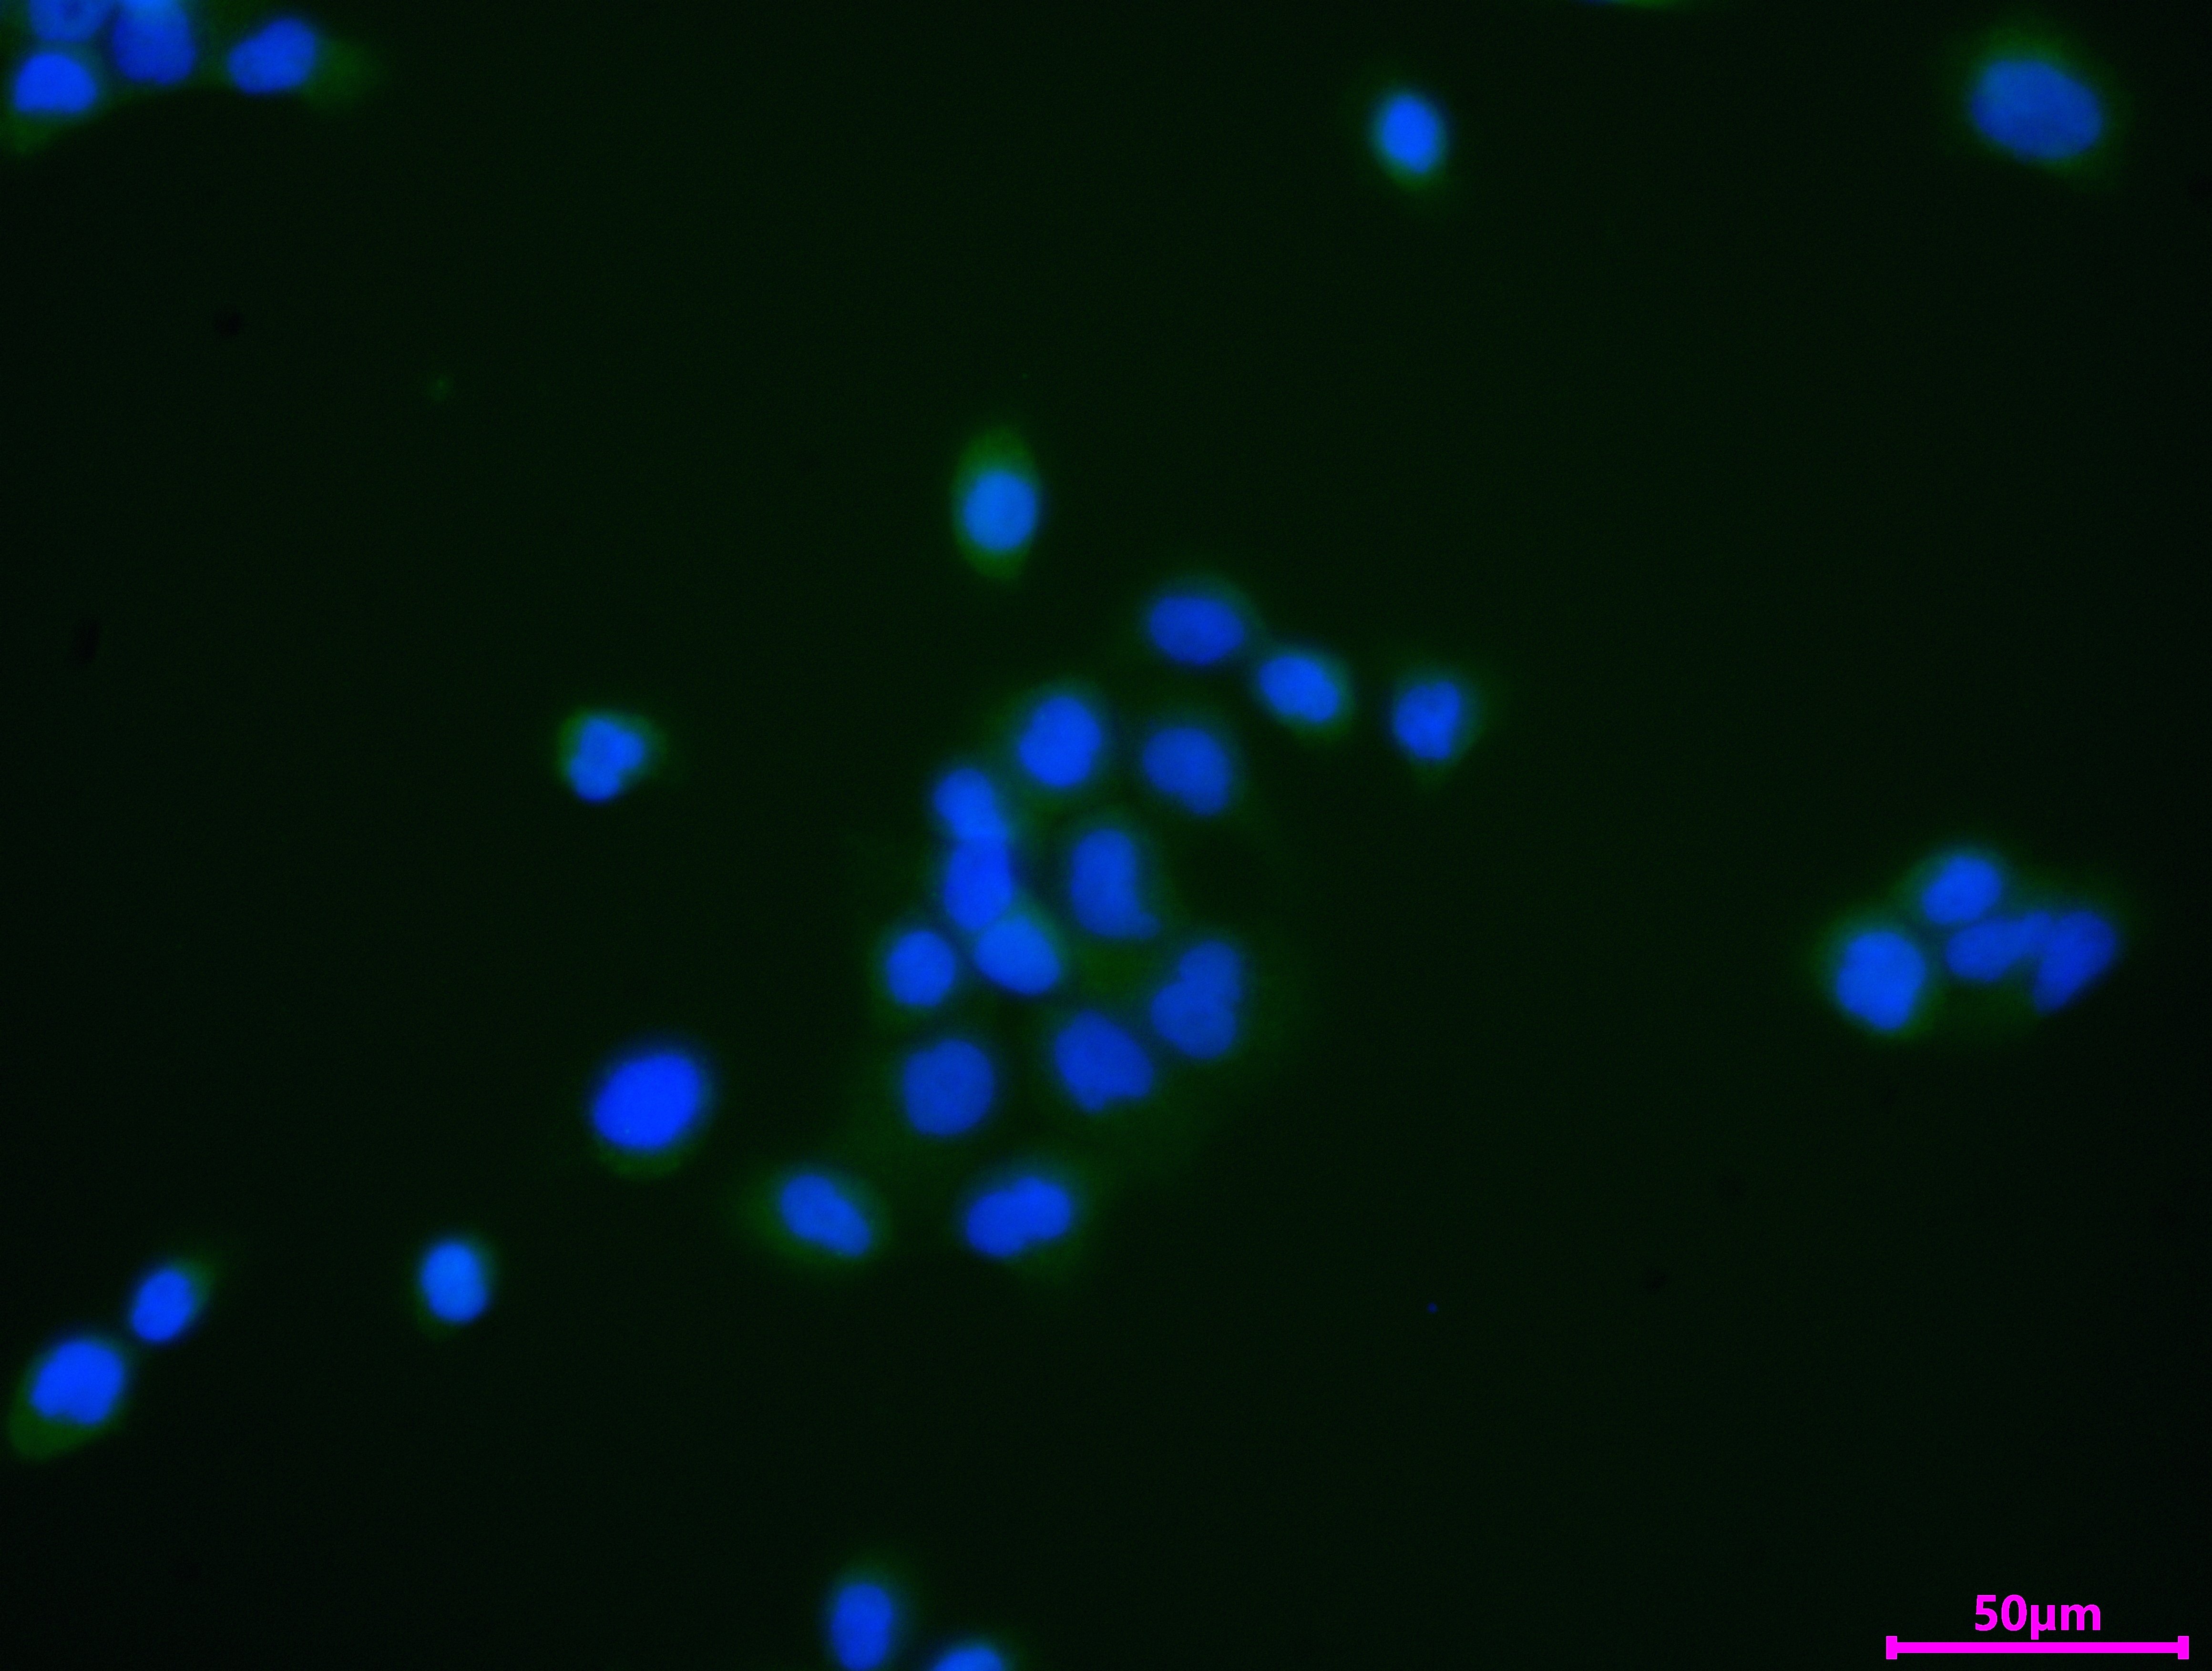

Immunofluorescence staining of PC-3 cell with CSB-PA015249LA01HU at 1:30, counter-stained with DAPI. The cells were fixed in 4% formaldehyde and and permeated by 0.2% TritonX-100 for 15 min. Then 10% normal goat serum to block non-specific protein-protein interactions . The cells were then incubated with the antibody overnight at 4℃. The secondary antibody was Alexa Fluor 488-congugated AffiniPure Goat Anti-Rabbit IgG(H+L).

Immunofluorescence staining of PC-3 cell with 5% goat serum, counter-stained with DAPI. The cells were fixed in 4% formaldehyde and blocked in 10% normal Goat Serum. The cells were then incubated with the antibody overnight at 4C. The secondary antibody was Alexa Fluor 488-congugated AffiniPure Goat Anti-Rabbit IgG(H+L).